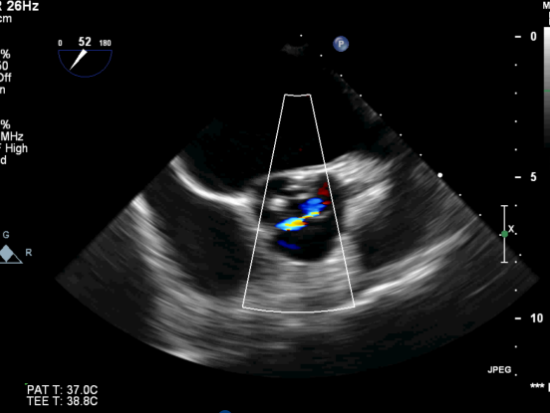

图1. 主动脉瓣钙化明显,并中量反流

图2.CDFI示主动脉瓣血流信号呈“五彩”样,CW示过瓣流速明显增快

图6.TEE提示未见瓣周漏,CW示过瓣流速较术前明显下降